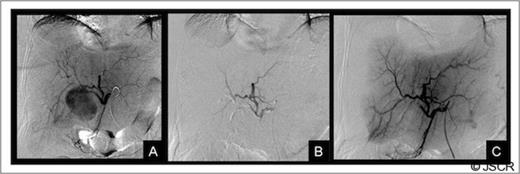

Forty-eight hours after admission the patient had an episode of haemodynamic instability suggestive of septic shock, which was also associated with a drop of 15 points in haematocrit levels (haematocrit: 24, WBC: 33 000). Empirical antibiotic therapy was begun and abdominal contrast-enhanced computed tomography (CT) was performed. CT showed a pseudoaneurysm of the right hepatic artery (RHA) of 7 cm in diameter, haemoperitoneum, intrahepatic dilatation of the biliary tree bile duct and the presence of hepatic infarction, and duodenal wall involvement (Figures 1 and 2).

CT of the abdomen: Complications of the pseudoaneurysm A, B) Hepatic infarction C)Duodenal wall involvement, D) Hemoperitoneum under right hemidiaphragm.